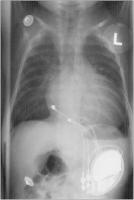

Abbildung 1: Größenverhältnis eines Zweikammerschrittmachers mit unipolaren epikardialen Elektroden bei einem 3 Monate alten Säugling. Der Patient hatte nach einer Korrektur eines AV-Kanals einen kompletten AV-Block behalten. 4 Monate später kam es zur Perforation der Schrittmachertasche. Bei einem Gewicht von weniger als 10 kg wurde erfolgreich ein transvenöses bipolares Zweikammerschrittmachersystem implantiert.